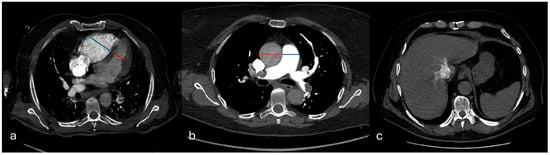

(1) Background: Pulmonary embolism (PE) represents the third most important cardiovascular cause of death after myocardial infarction and stroke. The proper management of this condition is dependent on adequate risk stratification, due to the life-threatening complications of more aggressive therapies such as thrombolysis. Copeptin is a surrogate marker of vasopressin which is found increased in several cardiovascular conditions. The Mastora score is an imagistic evaluation of the degree of pulmonary arteries thrombotic burden based on computed tomography angiography. In this study, we aimed to evaluate the diagnostic and prognostic role of copeptin in patients with acute PE. Furthermore, we analyzed the relationship between copeptin and Mastora score and their role in PE risk profiling. (2) Methods: We conducted a single center prospective study that included 112 patients with PE and 53 healthy volunteers. Clinical and paraclinical parameters, together with plasma levels of copeptin and the Mastora score, were evaluated in all patients after admission. (3) Results: Copeptin levels were significantly increased in PE patients compared with the general population (26.05 vs. 9.5 pmol/L, p < 0.001), while receiver operating characteristic (ROC) analysis revealed an AUC of 0.800 (95% CI 0.728–0.873, p < 0.001). Copeptin directly correlated with the Mastora score (r = 0.535, p = 0.011) and both parameters were strong predictors for adverse clinical events and death. Receiver operating characteristic (ROC) analysis for death within 30 days revealed a copeptin cut-off of 38.36 pmol/L, which presented a specificity of 79.6% and a sensitivity of 88.9%, and a Mastora score cut-off of 82 points, which presented a specificity of 74.8% and a sensitivity of 77.8%. (4) Conclusions: Our results showed that copeptin and the Mastora score are both correlated with adverse cardiovascular events and mortality in PE patients, and this may pave the way for their use in clinical practice, helping physicians to select the best therapeutical management. Full article

Figure 1